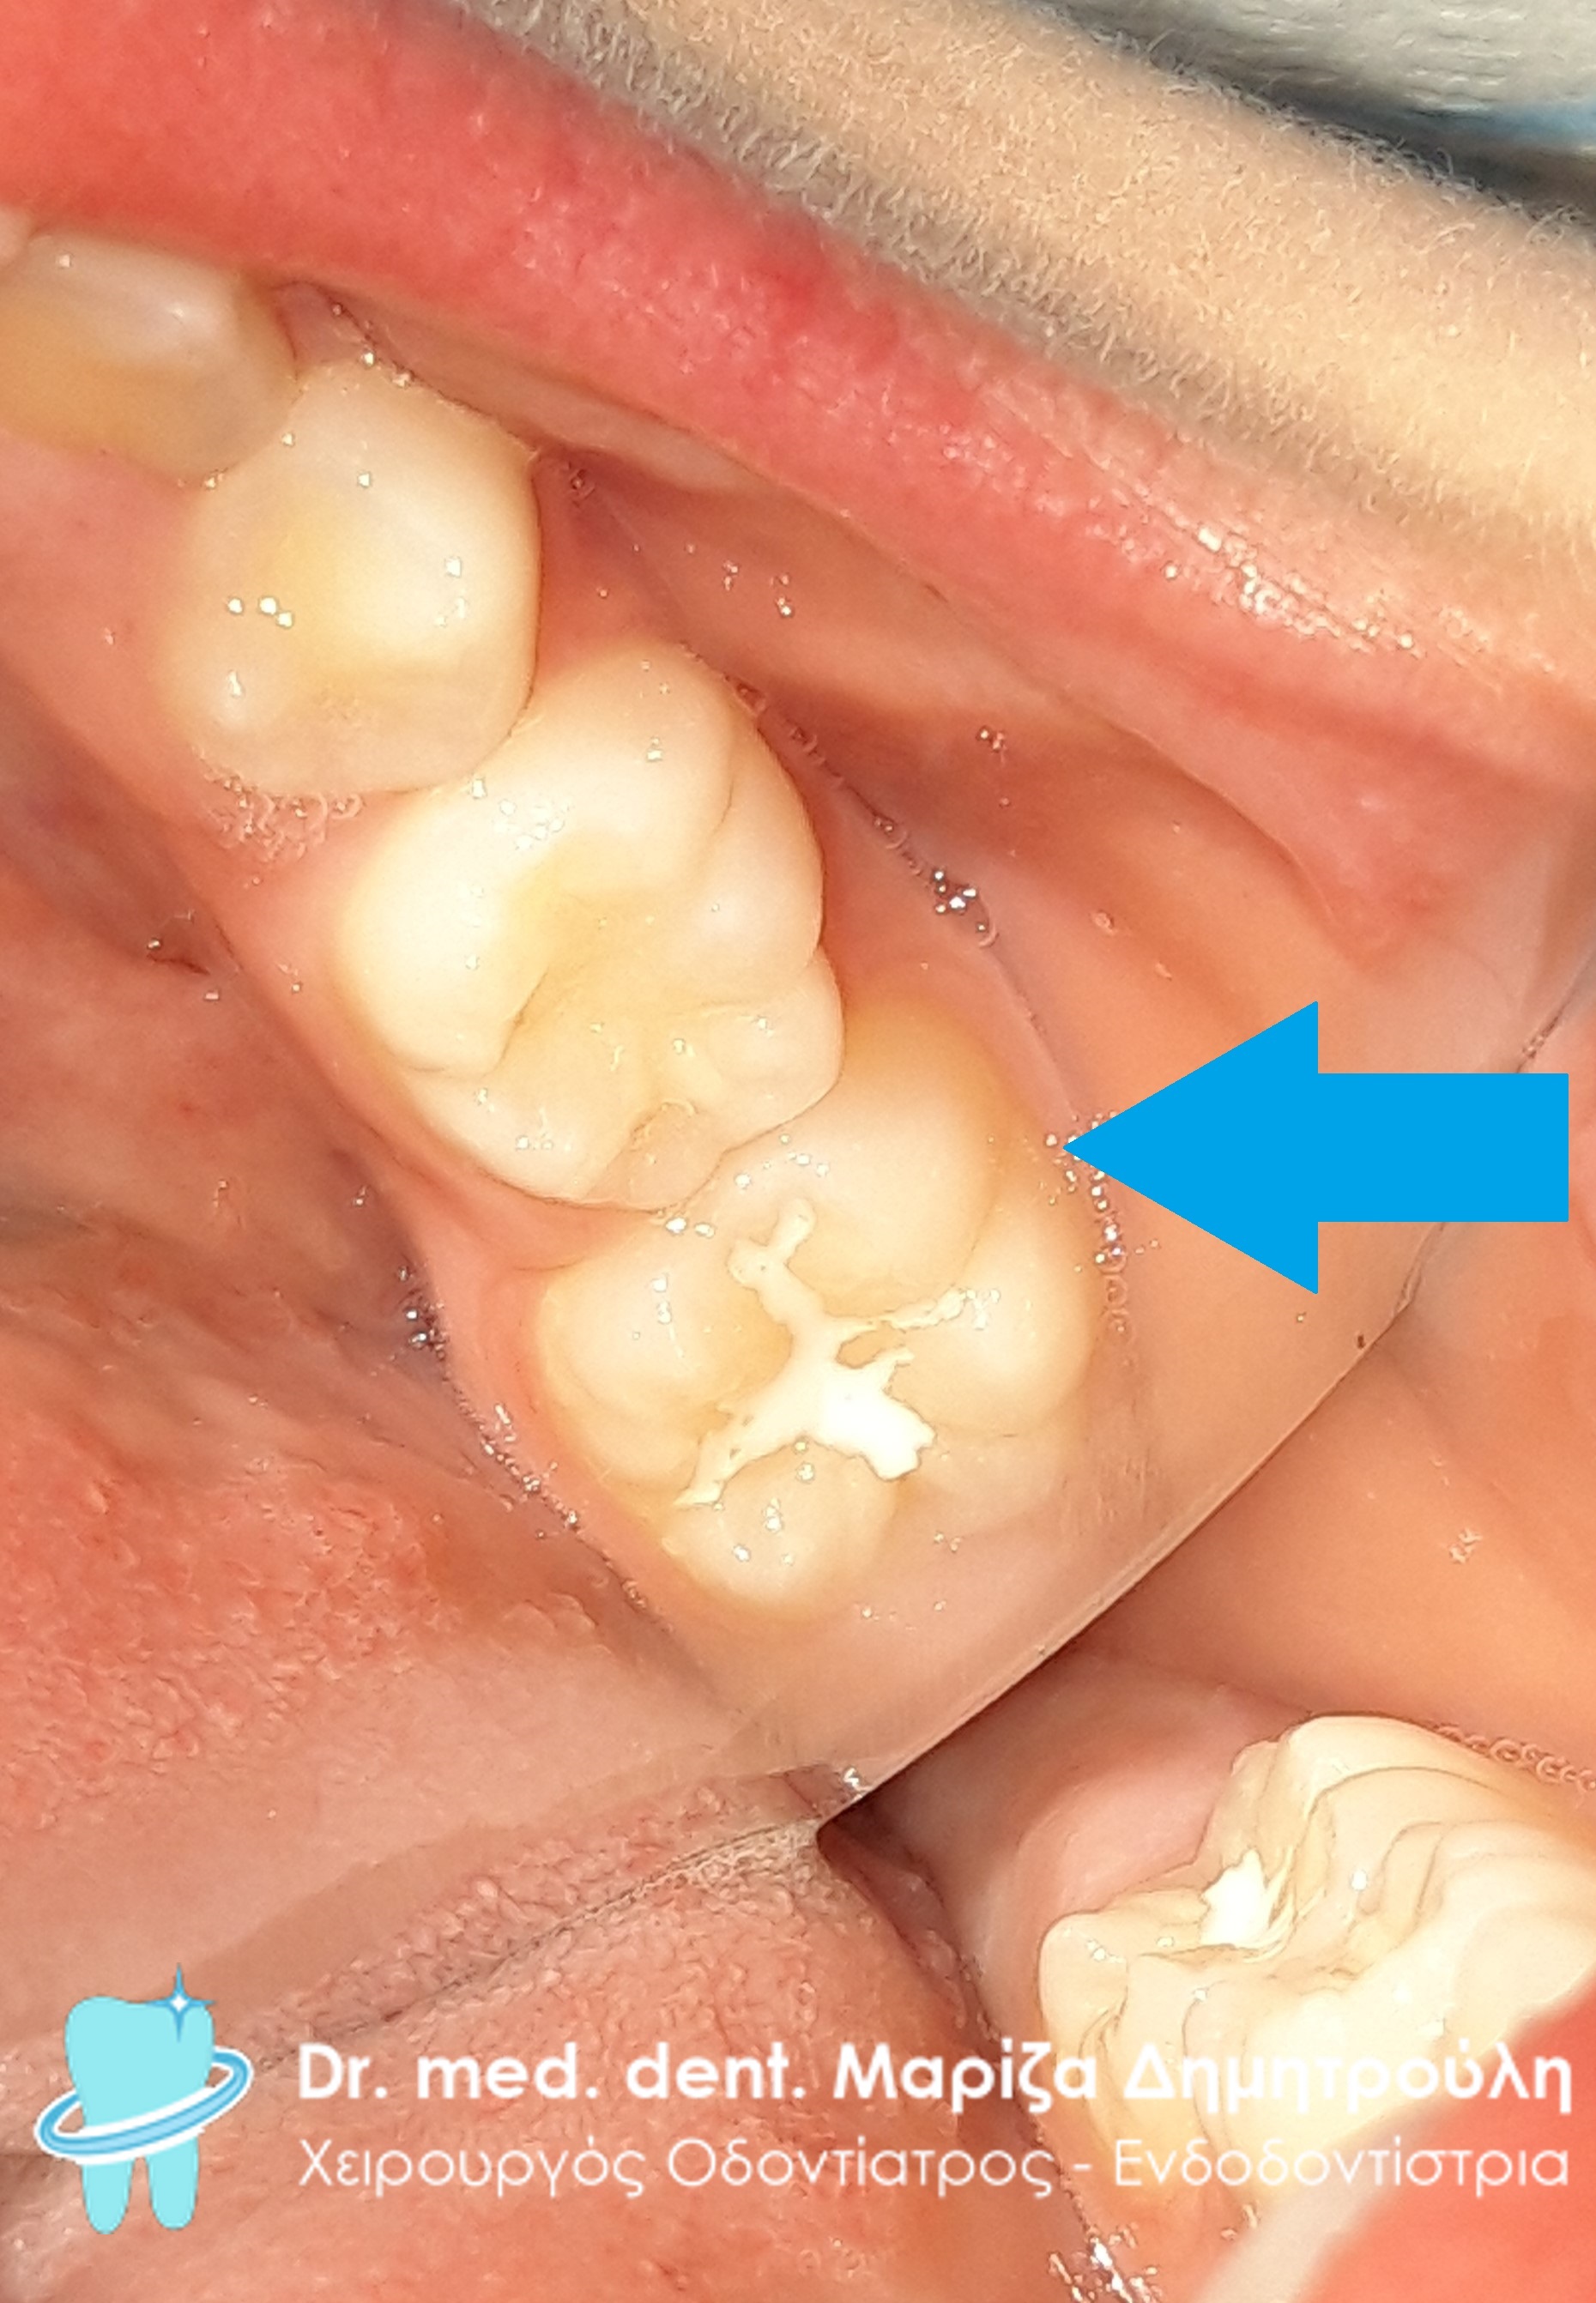

Κατά την κλινική εξέταση του μικρού αυτού αγοριού διαπιστώθηκε μία μικρή αρχόμενη τερηδόνα στον πρώτο αριστερό μόνιμο γομφίο της άνω γνάθου ενώ από στο δεύτερο νεογιλό γομφίο υπήρχε μία μικρή κοιλότητα που δε φαίνεται ευκρινώς στη συγκεκριμένη φωτογραφία. Το περιστατικό αντιμετωπίστηκε με την προληπτική κάλυψη οπών και σχισμών (sealant) στη μασητική επιφάνεια του πρώτου μόνιμου γομφίου και τη δημιουργία λευκού σφραγίσματος στο δεύτερο νεογιλό γομφίο.

Περιστατικό – Σφράγισμα νεογιλού δοντιού και sealant / προληπτική κάλυψη οπών και σχισμών